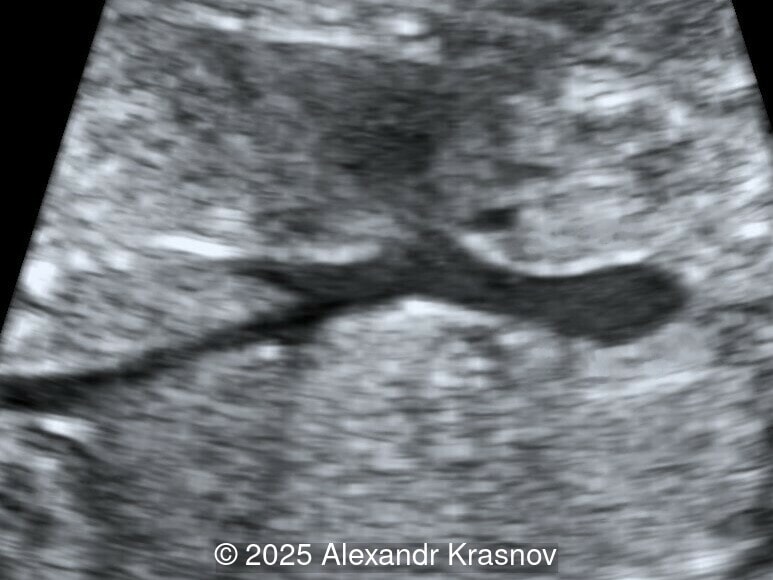

Image 4

Our ultrasound showed biometry data corresponding to 21 weeks of gestation. During echocardiography, an abnormal drainage of the pulmonary veins was detected in which the pulmonary veins drain into a venous collector linked to the superior vena cava. The four-chamber view and the three-vessel view were altered and raised suspicion of a pathology. The grayscale and color Doppler images of the four-chamber view indicate a smooth posterior wall of the left atrium, increased distance between the left atrium and the descending aorta and the absence of pulmonary veins entering the left atrium (Image 1, 2; Video 1, 2). In the three-vessel view, the diameter of the superior vena cava appears larger than that of the aorta (Image 3, Video 3). In the images of the venae cava, a significant difference is seen between the diameters of the inferior and superior vena cava with significant enlargement of the superior vena cava (Image 4, Video 4). Additionally, there is a pulmonary venous confluent chamber (“twig sign”) behind the left atrium (Image and Video 5). A vertical ascending vein connects the confluent chamber with the superior vena cava where it drains blood from the pulmonary veins (Images 6, 7; Video 6).